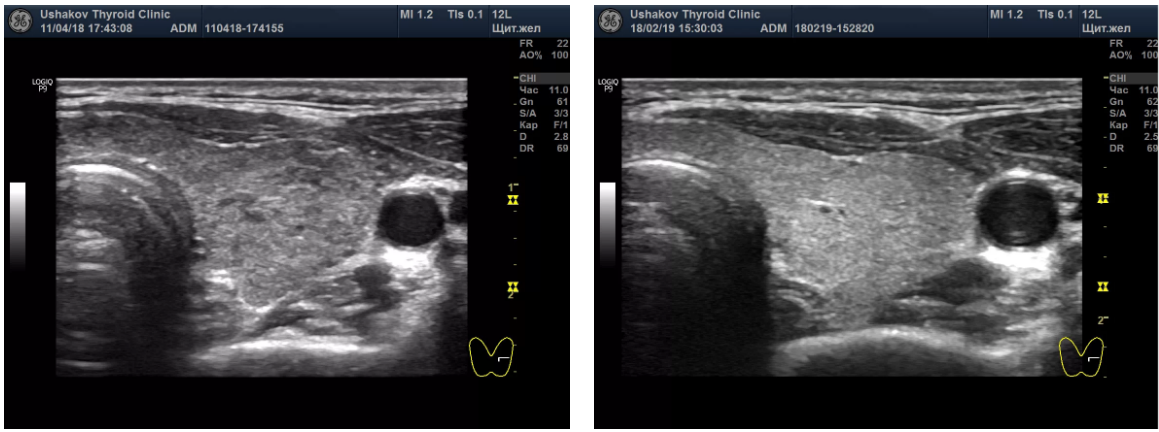

Пример восстановления щитовидной железы при болезни Грейвса в Клинике щитовидной железы доктора А.В. Ушакова. Слева до лечения:, справа - после лечения. Американские коллеги считают это состояние неизлечимым. Понятно почему... Если не лечить, то и результата не будет.